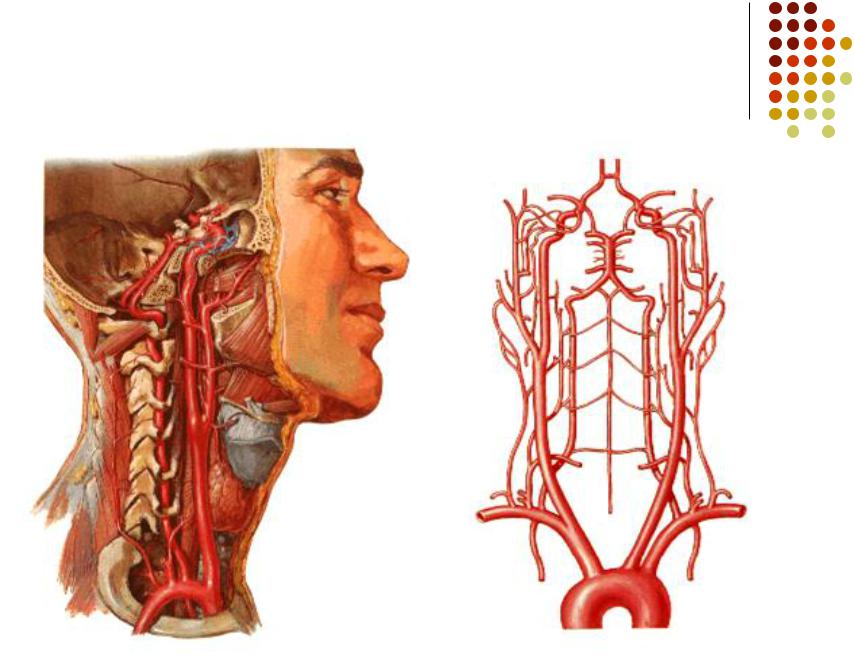

Анатомия: Задняя соединительная артерия мозга

:max_bytes(150000):strip_icc()/CircleofWillis-87378170-3ece0502a02949dd82310d723e0d4c98.jpg)